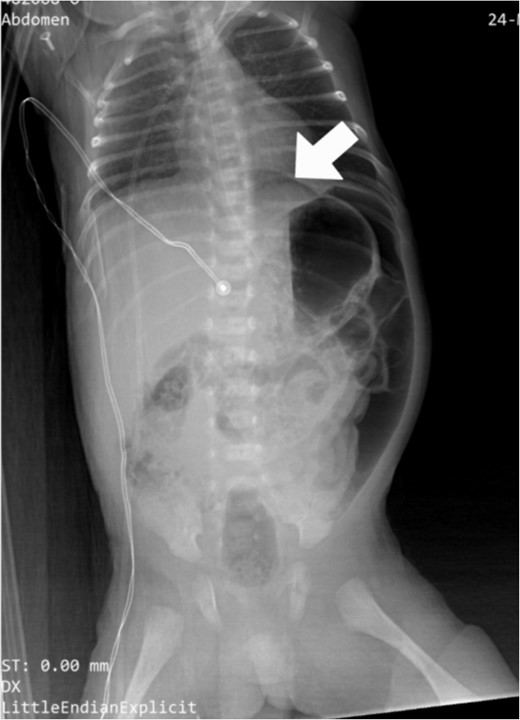

The CBC showed that the white blood cell count was 2.1 × 109 cells/L, the platelet count was 276 ×109 cells/L, and the CRP level was 5.2 mg/dl. There was no occult blood in the stool, the ABG showed mild metabolic acidosis with a lactate level of 3.46, and an abdominal X-ray showed pneumoperitoneum with increased abdominal distension (Fig. 1). The decision to perform an emergent exploratory transverse laparotomy was made with a presumed diagnosis of intestinal perforation as a complication of NEC.

Preoperative abdominal X-ray: lateral decubitus view showing pneumoperitoneum (white arrows).